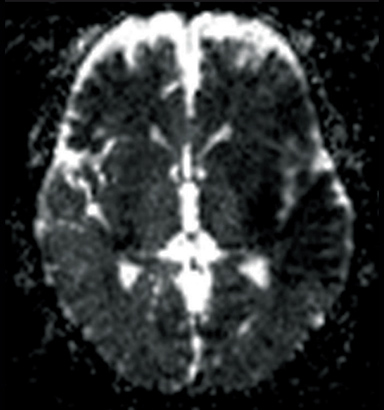

ADC map